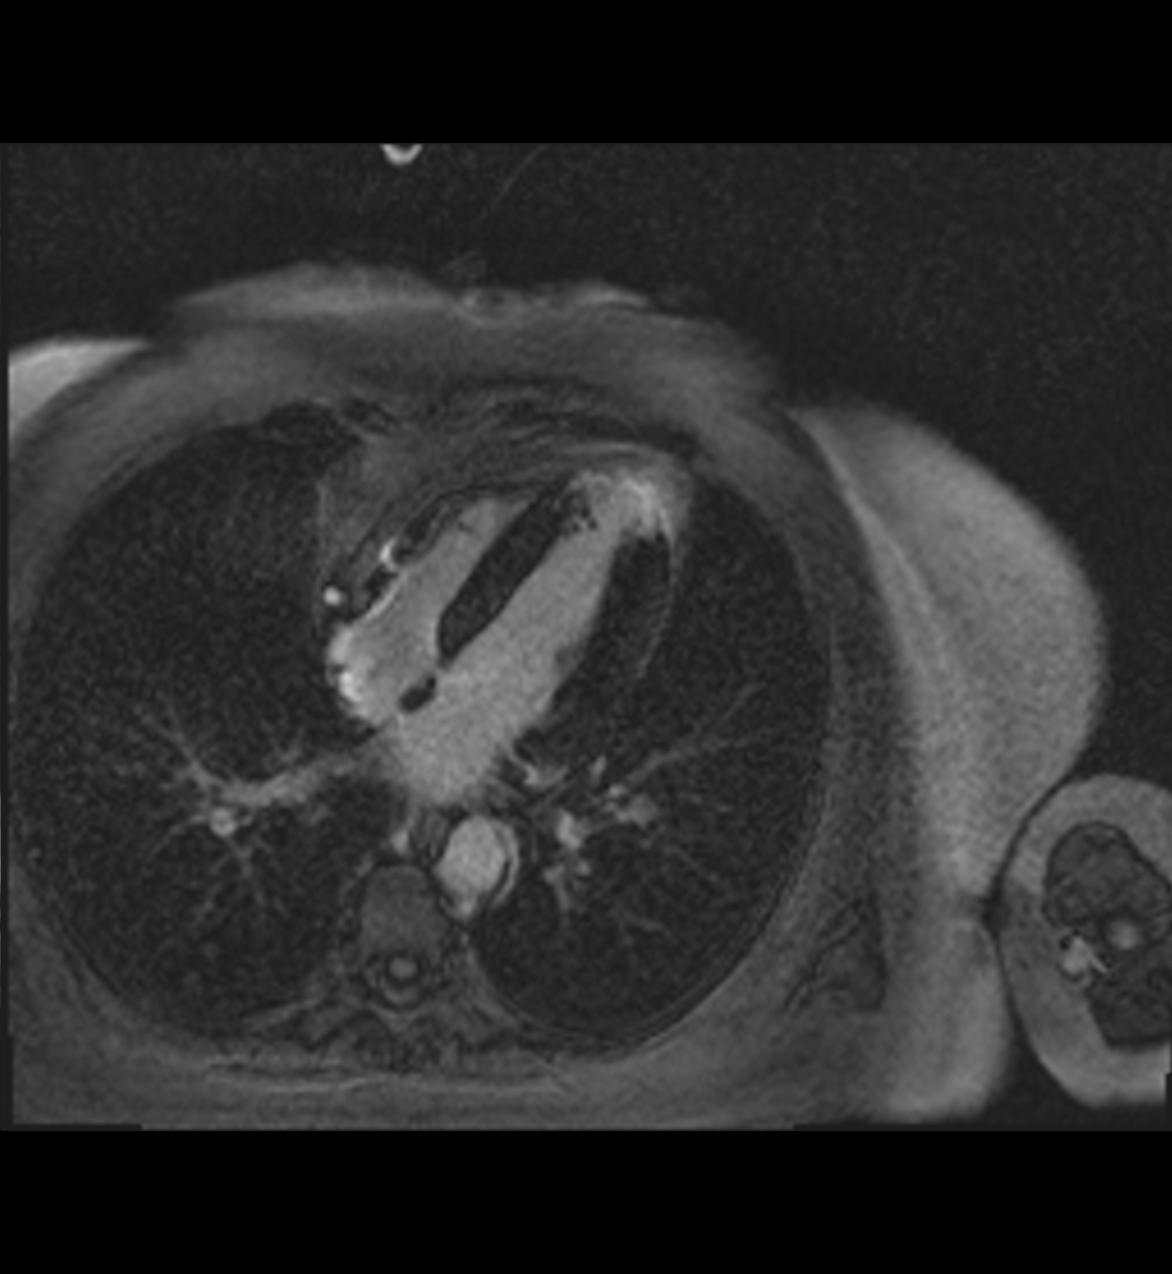

Die Magnet-Resonanz-Tomographie der Brust ist das Verfahren, mit dem ohne Röntgenstrahlen am genauesten Veränderungen des Brustgewebes erkannt werden können.

Obwohl keine weiteren Fragestellungen offiziell von den Krankenkassen zugelassen sind, ist das Verfahren noch in etlichen weiteren Fällen sinnvoll. Ein Beispiel dafür ist die Frage, ob neben einem bekannten Krebsherd noch weitere z.B. sehr kleeine bösartige Prozesse in der Brust vorhanden sind. Manchmal werden solche weiteren Herde erst durch eine präoperative MRT entdeckt. Auch bei Brustimplantaten ist die Methode eine wichtige diagnostische Ergänzung, nicht nur zur Aufdeckung von Tumoren, sondern auch mit der Frage nach einem Implantatdefekt. Auch die Therapiekontrolle bei Patientinnen, die vor einer Operation mit einer Chemotherapie behandelt werden („neoadiuvante Therapie“), sollte mit der Kernspintomographie erfolgen. Dabei zeigt sich sehr viel genauer als in der Röntgenmammographie, ob der Tumor auf die Chemotherapie anspricht.

Die Datenakquisition und –auswertung in der MRM ist besonders aufwendig und erfordert spezielle Hard- und Software sowie besondere Erfahrung. Wir führen diese speziellen Techniken seit vielen Jahren mit erstklassischer Ausrüstung erfolgreich durch.

Die Patientin muss den Oberkörper im Untersuchungsraum ganz freimachen. Eine exakte Lagerung in Bauchlage ist hier besonders wichtig. Der Oberkörper wird direkt auf, die beiden Brüste, die immer im Seitenvergleich untersucht werden, direkt in die Spule hineingelagert und ausgepolstert. Da im Rahmen der Bildnachverarbeitung die Bildserien vor der intravenösen Kontrastmittelgabe von denen danach subtrahiert werden, ist es besonders wichtig, vollständig ruhig zu liegen, um keine Subtraktionsartefakte zu erhalten, die die Bildauswertung erschweren oder unmöglich machen.